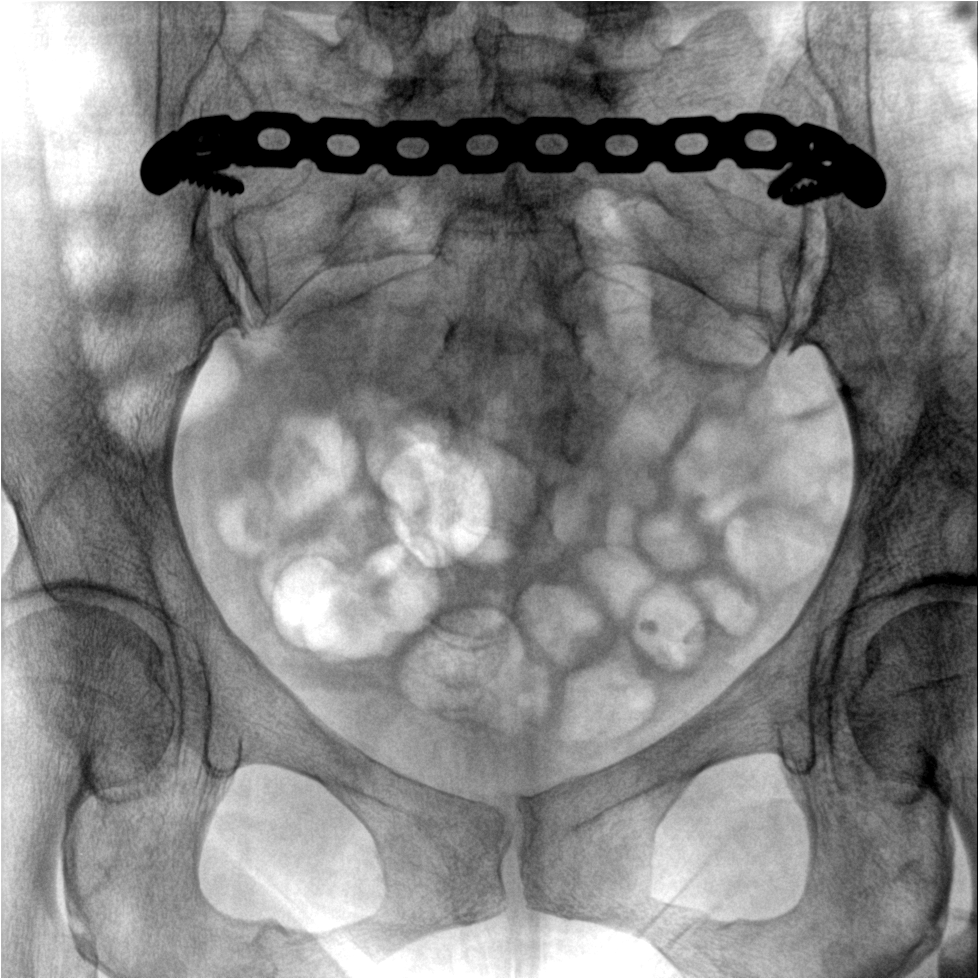

術(shù)中三維成像和橫斷面圖像提供多角度的手術(shù)診斷信息,輔助醫(yī)生進行術(shù)中評估判斷,諸如骨折復位情況和內(nèi)植入螺釘?shù)某叽绾臀恢茫o助手術(shù)更好地完成。

提供更大的術(shù)中三維成像視野,采集更多圖像信息,可一次拍全全段頸椎、全段腰椎、七節(jié)胸椎、雙側(cè)骶髂關(guān)節(jié)、股骨頭及單側(cè)盆骨。